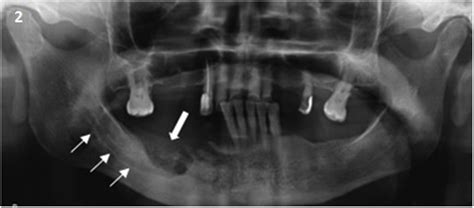

Ortopantomografía correspondiente al mismo paciente, donde se puede apreciar área de osteolisis en la región del ángulo mandibular derecho.